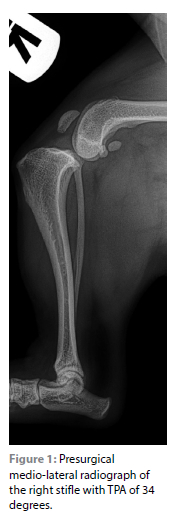

Radiographs revealed cranial tibial subluxation of the stifle joint with cranially displaced intercondylar eminences in relation to the femoral condyles, marked joint effusion with obliteration of the infrapatellar fat pad, displacement of the popliteal sesamoid and small supratrochlear osteophytes of the distal femur (Figure 1).

No distal femoral varus deformity was present based on the measurement of the lateral distal femoral angle, which indicated that no distal femoral ostectomy for addressing the medial patellar luxation was required (Tomlinson et al. 2007). No external femoral torsion was appreciated. There was, however, medial displacement of TT as defined by the positive quadriceps angle reported in a previous study (Towle et al. 2005). A tibial plateau angle (TPA) of 34 degrees was measured on the medial-lateral radiograph. A decision was made to do a mCCWO and TTT to address both conditions simultaneously.